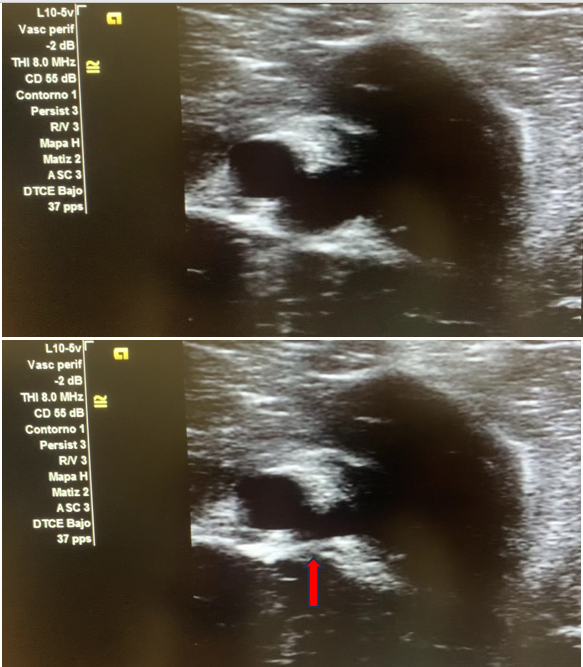

Imagen 1. Muslo derecho, lesión de bala.

Imagen 2. Vasos no colapsables, con internior anecoico.